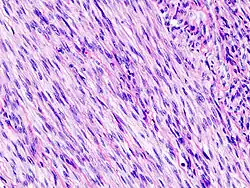

Leiomyom

Leiomyome sind gutartige (benigne) Tumoren der glatten Muskulatur. Die Bezeichnung leitet sich her von altgriechisch λεῖος leîos, ‚glatt, sanft‘ und μῦς mŷs, ‚Muskel‘ und -om „Geschwulst“.

Die glatte Muskulatur bildet sich während der Entwicklung eines Lebewesens aus mesenchymalen Zellen. Die Leiomyome werden daher auch zur großen Gruppe der benignen mesenchymalen Tumoren zugeordnet. Die häufigste Lokalisation von Leiomyomen des Menschen ist mit etwa 90 % die Gebärmutter, solche Tumoren werden als Uterusmyome bezeichnet. Daneben können Leiomyome in allen Organen entstehen, die Anteile glatter Muskulatur haben, wie beispielsweise Leiomyome der Gefäße (Angioleiomyome), der Hautanhangsgebilde (Dermatoleiomyome), der Speiseröhre (Ösophagusleiomyome) und der ableitenden Harnwege. Auch intrakranielle Leiomyome wurden in Einzelfällen beschrieben.[1]